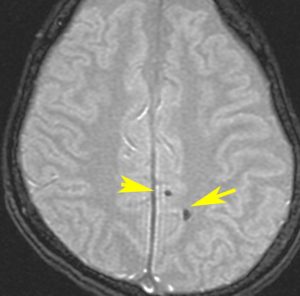

海綿状血管腫 微小血管障害

多発性微小脳出血

- ほとんどが小児に生じるものです

- 放射線治療を受けた患者の40%くらいでみられます

- 照射後10年くらい長期観察をしていると実際に非常に高頻度にみます

- 海綿状血管腫は,放射線誘発2次腫瘍というよりも,放射線による脳内小血管損傷による血管障害として捉えた方がよいです

- T2スターというMRI画像で発見できます

11歳の時に全脳室照射24グレイ・12分割を受けた女の子です。10年以上経過して,脳のあちこちに小さな黒い点状のものが見えるようになってきました。これは子供の頃に放射線治療を受けた人に多く,なんでもないもので症状は出ませんし,ほっておいていいものです。微小な脳静脈の放射線損傷による血液の漏れだと考えられています。

- 低信号(黒いシミみたいなもの)として脳内たくさん見られることがあります

- これは血液の中の鉄分が脳に滲み込んだ形跡をみているものです

- だから,海綿状血管腫とは言わないで,blood leak(血液が漏れた痕跡)と読んだ方がいいものです

- 海綿状血管腫というと腫瘍みたいだからです

- 年月の経過とともに数が増加します

- 海綿状血管腫は発生しても何ら症状を呈することはありません

- 治療をせずに放置します

- まれに小さな脳出血を生じますが,経過を見れば血腫は自然に吸収されます